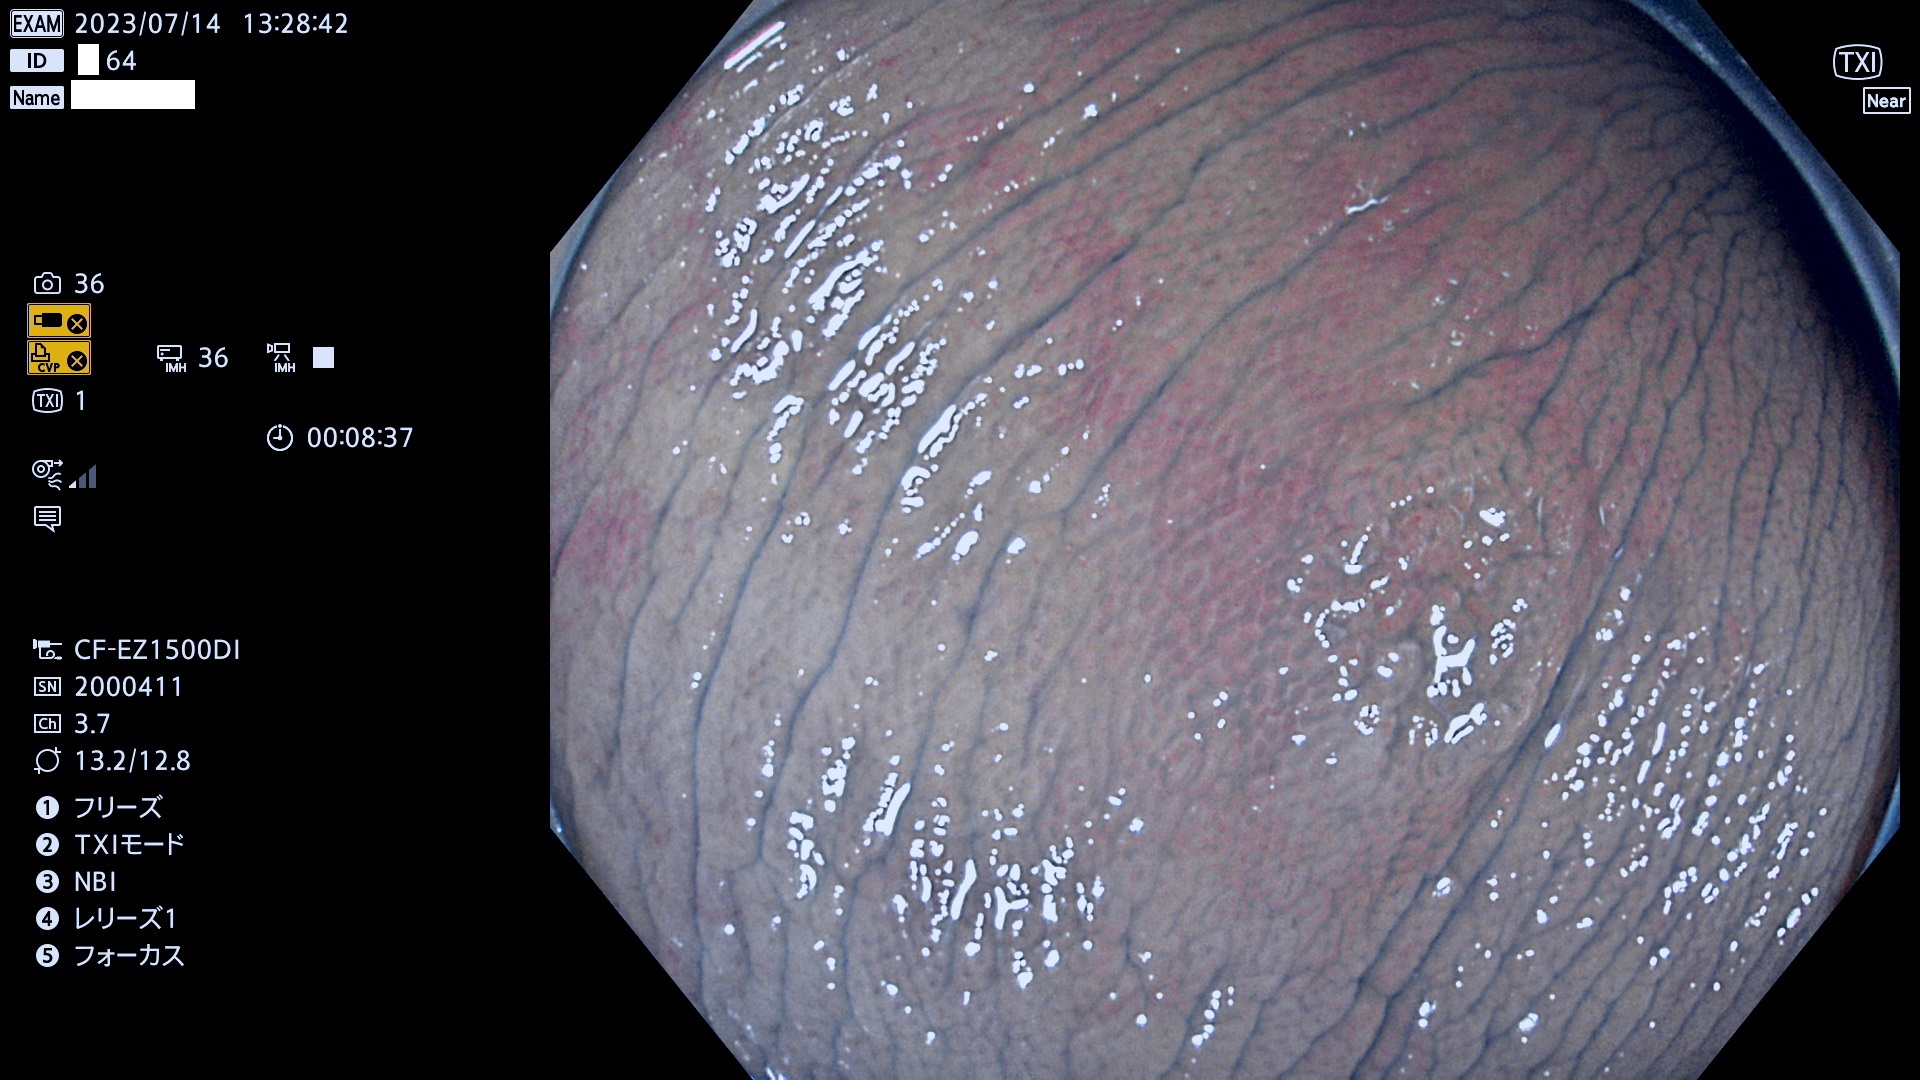

大腸Ub、Uc型・腺腫とは?

「表面型腺腫(Flat Adenoma)の中で、完全に平坦な物をUb、陥凹している物をUcと呼びます。平坦隆起型(Ua)よりも、発見が難しく危険な病変です。このタイプの発見率は「腺腫発見率」よりも、遥かに重要な意義があります。

毎週の検査(木・金・土・日)に発見されたUb、Uc型・腺腫を、その週の日曜の夜にUPし1週間、提示します。

抽出の対象期間 2023年7月13日(木)〜7月16(日)の4日間(48件の検査)8件